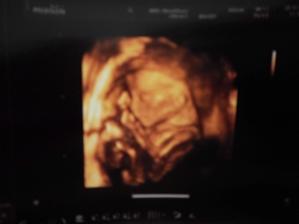

- 29.12.2015 - Kontrola, ultrazvuk. První 3D fotka. Adélka je zdravá a nic ji nedorostlo - potvrzení 100 % holčičky ;)